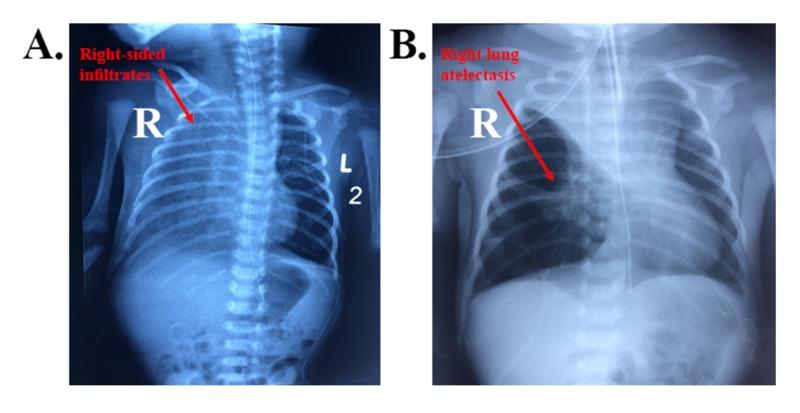

Pulmonary artery sling is a rare cause of neonatal respiratory distress. Most patients with pulmonary artery sling present in early infancy with stridor and signs of respiratory distress. Diagnosis of pulmonary artery sling, like other vascular ring anomalies, can be made using various imaging modalities, and management encompasses urgent surgical repair as a definitive treatment. This is the first paper to report a successfully managed case of an early detected left pulmonary artery sling during the first week of life in a term male patient and to evaluate the diagnostic characteristics in alliance with it. CAse REports (CARE) guidelines were followed for reporting our case. In brief, a case of full-term baby boy was born by normal vaginal delivery and shortly after birth, the baby started to have respiratory distress not improving on O. Chest X-ray revealed right upper lobe atelectasis which persisted despite mechanical ventilation and antibiotics. A thoracic CT scan showed developmental malformation of left main pulmonary artery, confirming the diagnosis of "left pulmonary artery sling." The baby was immediately operated. One week later, chest X-ray showed gradual improvement and the baby was discharged home with no postoperative complications. Hence, we suggest that pulmonary artery sling should be suspected in any neonate with respiratory distress and unilateral lung field opacification. The fact that there are only very few reports on this disease raises a need to establish and implement well-defined guidelines and criteria for early diagnosis and management of pulmonary artery sling among newborns.